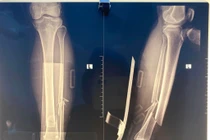

Sau khi thăm khám và chụp chiếu, các bác sĩ chẩn đoán ông bị gãy cổ xương đùi bên phải, tình trạng rất nặng. Hơn nữa ông có rất nhiều bệnh nền như suy tim, tăng huyết áp, COPD… có thể làm cuộc mổ trở nên nguy hiểm, dễ dẫn đến suy tim, đột quỵ trong và sau phẫu thuật.

Không thể cử động chân, người đàn ông 71 tuổi gãy kín 2 xương

Gãy xương kín là hiện tượng xương gãy nhưng không đâm xuyên qua da nên thường được thực hiện điều trị muộn sau vài ngày hoặc vài tuần chấn thương.

Gãy cả 2 xương cẳng chân mà không biết

Vừa qua, các bác sĩ Khoa Ngoại – Trung tâm Y tế khu vực Phù Ninh đã phẫu thuật thành công cho người bệnh Đ.T.L (71 tuổi, trú tại xã Phù Ninh, tỉnh Phú Thọ) bị gãy kín hai xương cẳng chân trái sau tai nạn sinh hoạt.